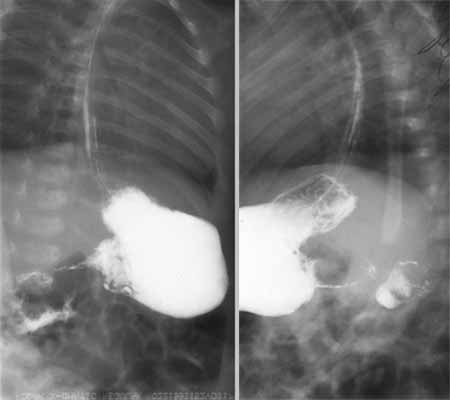

Врожденный пилоростеноз.

Рис. 2. Больной В., 1 мес. Врожденный пилоростеноз. Симптом «усика» или «жгутика». Вторичный гастроэзофагальный рефлюкс.